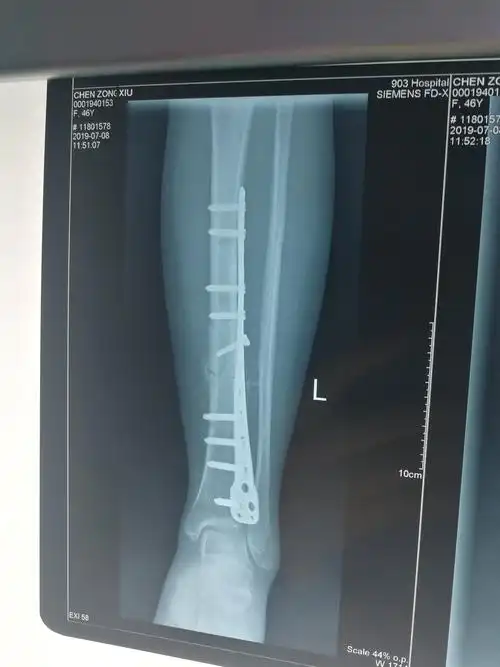

见左胫骨骨折端为纤维组织填充,无连续性骨痂,无明显的炎性渗出物